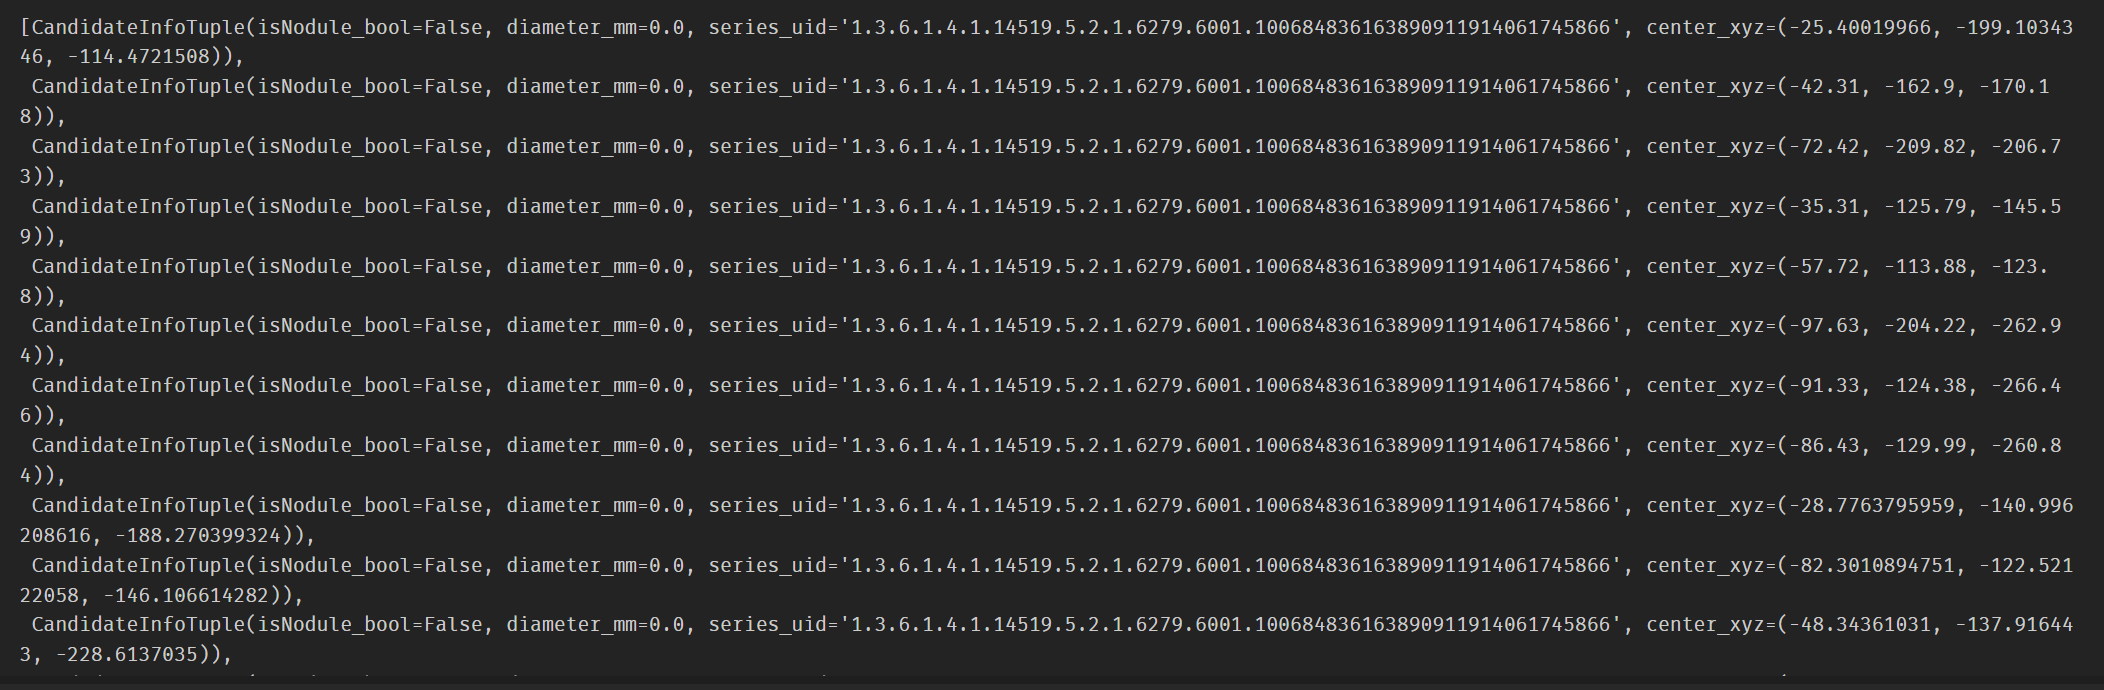

创建candidateInfo_list:

与diameter_dict类似,candidateInfo_list从candidates.csv中获取series_uid,center_xyz坐标信息,并存放在一个Tuple里,最终分类嵌入candidateInfo_list;

函数中设置了一些数据清洗的规则:

对于给定series_uid的每个候选条⽬,我们循环遍历之前为同⼀个series_uid收集的标注,看看2个坐标是否⾜够接近,如果⾜够接近则可以认为它们是相同的结节。如果是同⼀个结节,那太好了!现在我们有了这个结节的直径信息。如果没有找到匹配的结节,也没有关系,我们把结节的直径设置为0.